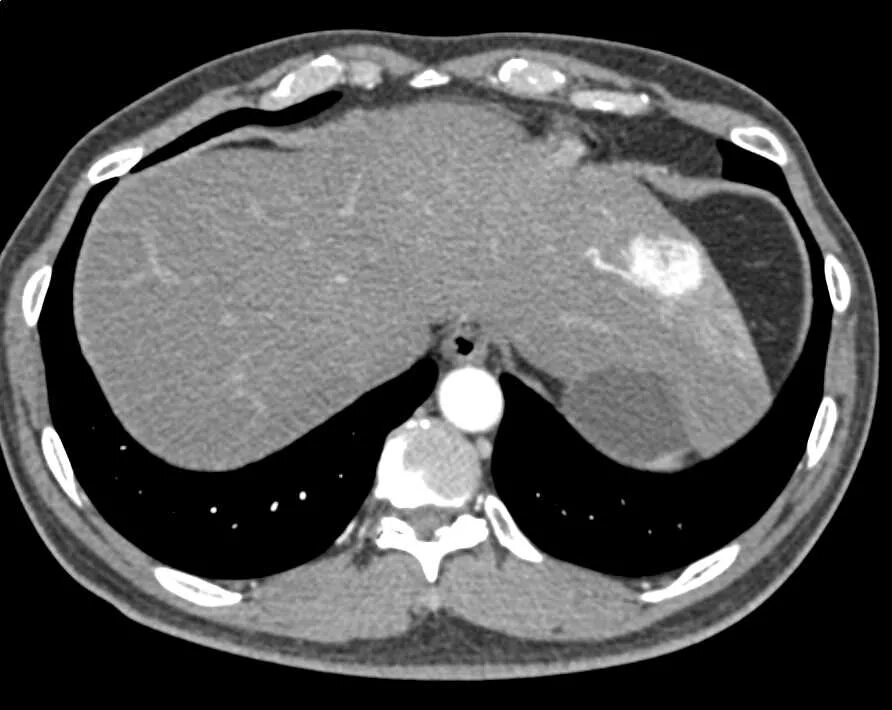

Образования печени кт